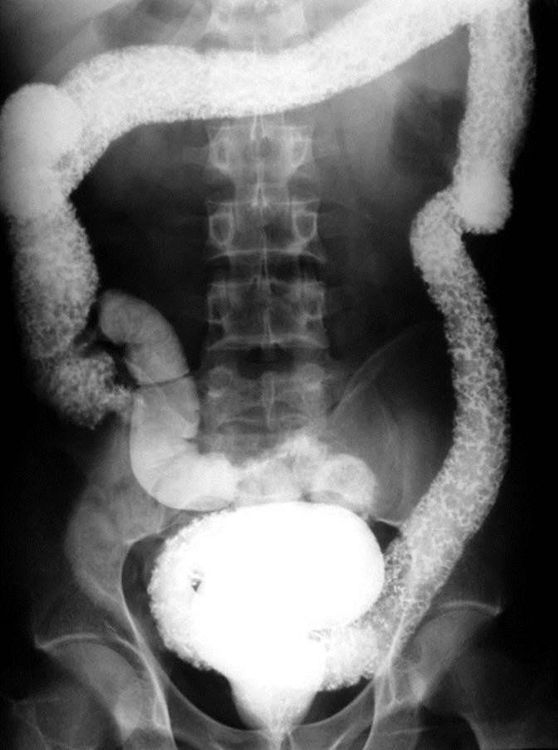

Sự phát triển của các phương pháp nội soi đã thay thế kỹ thuật chụp baryt trong chẩn đoán viêm loét đại tràng chảy máu. Tuy nhiên, trong một số trường hợp bệnh nhân nặng, chưa loại trừ được các biến chứng nguy hiểm như phình giãn đại tràng nhiễm độc, thủng đại tràng, tắc ruột, chụp baryt vẫn có giá trị thực tiễn. Ngoài ra, trên phim chụp không chuẩn bị có thể đánh giá khớp cùng chậu và đốt sống nếu bệnh nhân có triệu chứng đau lưng. Trên phim chụp baryt, các đặc điểm ghi nhận bao gồm niêm mạc thô, loét liên tục lan tỏa, đối xứng dọc từ trực tràng lên các đoạn phía trên của đại tràng, mất nếp gấp những đoạn đại tràng viêm.

Hình ảnh niêm mạc thô và mất nếp gấp trên chụp Bayt trong viêm loét đại tràng chảy máu.